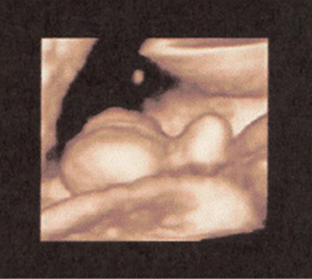

FIGURE 8–24. Three-dimensional sonogram of hand of a fetus at 29-weeks’ gestation. (Courtesy of Philips Healthcare.)